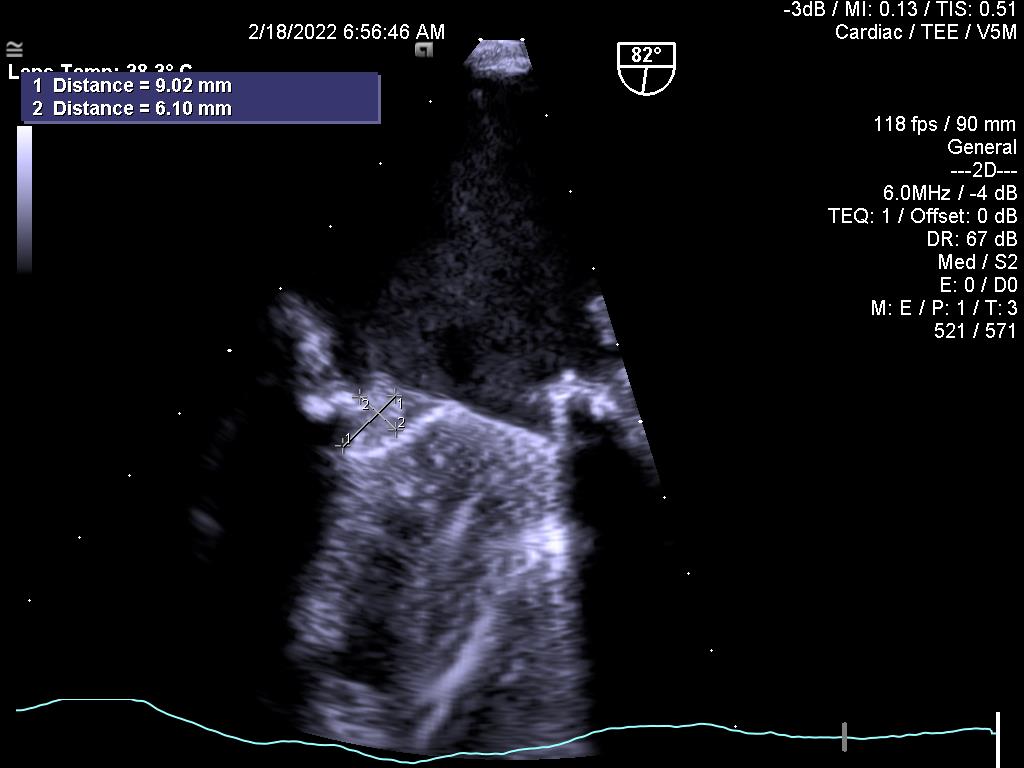

1.Huyết khối gây kẹt van hai lá cơ học:

2.Đánh giá hiệu quả điều trị bằng thuốc tiêu sợi huyết đối với kẹt van cơ học (cùng bệnh nhân ở trên)